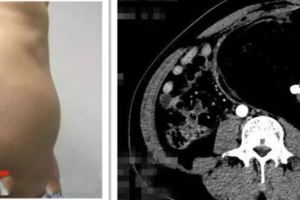

一男子9斤重肚腩減肥減不掉一查病因嚇一跳